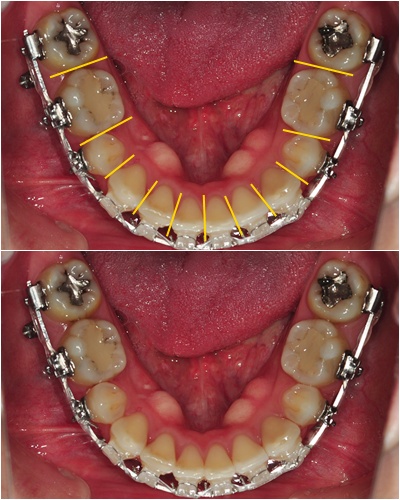

짜쟌~ 위에 사진처럼 치아 틈새마다 조금씩 갈아 주었어요~

아래 사진에 보시다시피... 정말 조금씩 얇게 갈아 낸 거라 티가 거의 안 나요~ ' ㅅ')!